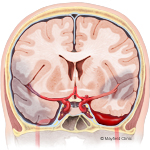

- Intracerebral hemorrhage ICH

Intracerebral hemorrhage (ICH) is caused by bleeding within the brain tissue itself - a life-threatening type of stroke. A stroke occurs when the brain is deprived of oxygen and blood supply. ICH is most commonly caused by hypertension, arteriovenous malformations, or head trauma. Treatment focuses on stopping the bleeding, removing the blood clot, and relieving the pressure on the brain.